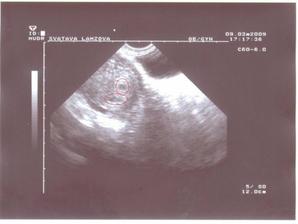

Po kontrole u paní doktorky nasazen utrogestan na udržení mimi, bublinka je tam, kde má být, naštěstí, ale paní doktorce se zdála nějaká dost malinká. Snad je to tím, že jsem měla pozdě ovu.... 9.3. jdeme na další utz, tak snad bude mimi větší... 9.3.2009 - kontrola potvrdila, že čekáme dvojčátka, dvojvaječná. Dle paní doktorky, ale ještě nejsou vidět plody, takže jdeme na další kontrolu 23.3. a doufáme, že už pořádně porostou a budeme mít i srdíčka 🙂 a máme první fotečku 🙂, od minule (2.3.) hodně porostly 🙂